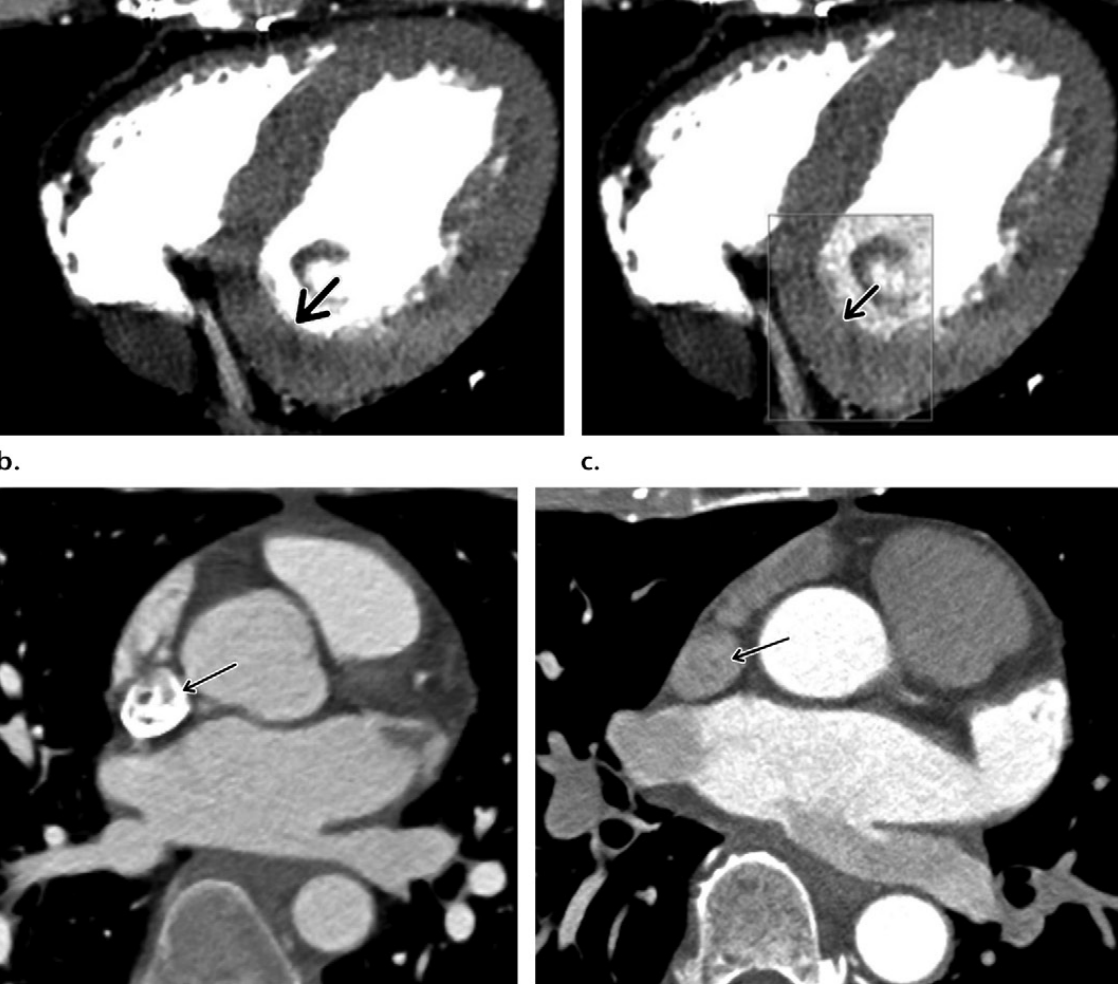

Describe the findings related to reduced image quality:

Body habitus –> noise artifact